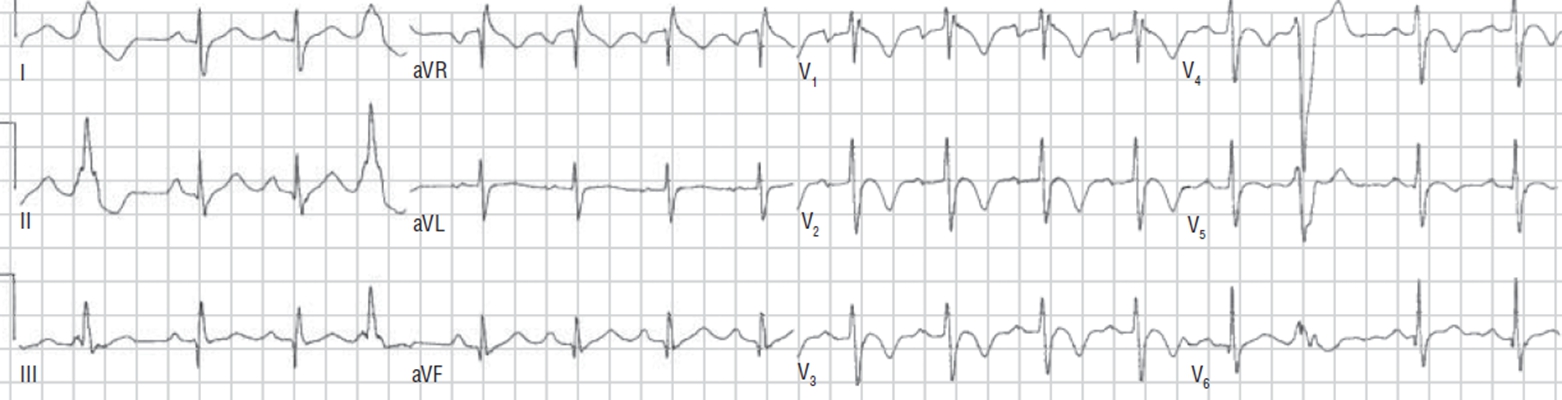

預激綜合徵心電圖 (79)

預激綜合徵心電圖 (8)

預激綜合徵心電圖 (80)

預激綜合徵心電圖 (81)

A:預激綜合徵合併房速的時候,心電圖可以出現快速而且寬大畸形的QRS波群,有點類似於室性心動過速,典型的預激波有可能會被覆蓋。合併房速的時候會有極快速的心室率、QRS波群會寬大畸形,也有可能比較易變和複雜。患有預激綜合症合併房速,如果有明顯的心……